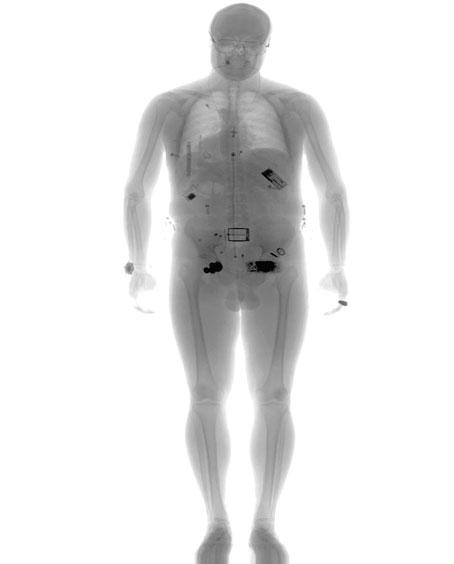

في الماسح الضوئي Secure 1000 الذي صنّعته شركة رابيسكان والذي يستخدم الأشعة المؤيّنة، يقف المسافر بين علبتين زرقاوتين كبيرتين لتُوجّه إليه حزمة من الأشعة السينية التي تتحرّك سريعاً من اليسار إلى اليمن ومن أعلى الجسد إلى أسفله. أما في الجهاز الثاني المدعو ProVision والذي صنعته شركة L-3 Communications المتخصصة في صناعة المعدّات الدفاعية، يدخل المسافر إلى غرفة تشبه كشك هاتف دائري الشكل ويخضع لمسح بواسطة موجات الميلمتر التي تعدّ أحد أشكال الموجات اللاسلكية المنخفضة الطاقة التي لم تُظهر الدراسات أنها تفصل الإلكترونات عن الذرات أو أنها تتسبّب بالسرطان.

أظهرت هذه الاختبارات أن جهاز Secure 1000 يصدر كمية صغيرة جداً من الأشعة تقل عن 10 ميكروريم. وتشكل هذه الكمية ما يقارب الواحد بالألف من كمية الأشعة السينية الستخدمة لتصوير الصدر، فيما تساوي كمية الأشعة الكونية المتلقاة في بضع دقائق من الطيران على ارتفاع نموذجي. وكانت إدارة أمن المواصلات قد استخدمت هذه الأرقام لتظهر أن الآلات «آمنة».